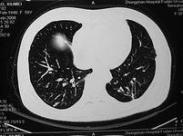

壞死性結節病樣肉芽腫病

• 壞死性結節病樣肉芽腫病